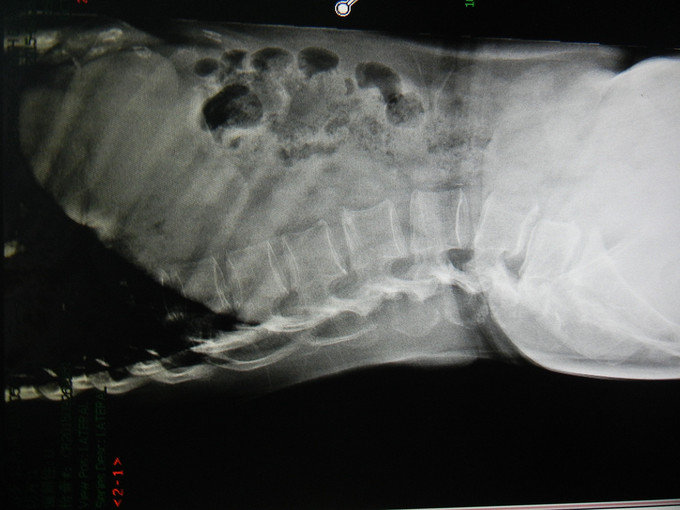

患者女,58岁。因“腰痛4年余”入院。现病史:患者于2011年出现腰部疼痛,伴左臂部疼痛,偶有左下肢麻木,无腹痛腹胀,无胸闷心慌,无恶心呕吐,未在当地治疗,辅助检查:腰椎MRI提示L5椎体滑脱,压迫相应硬脊膜,门诊以“腰椎滑脱”收入院。病程中一般情况可。

查体:心肺腹体检未见明显异常。专科情况:步入病房,脊柱生理曲度变直,表面皮肤未见破溃水肿,表浅静脉未见怒张。腰椎活动度检查:前屈50度,后倾20度,左侧曲度20度,右侧曲度20度。双下肢无明显感觉减退,左下肢髂腰肌、股四头肌、胫骨前肌,小腿腓肠肌,胫骨后肌,腓骨长短肌,拇趾长屈伸肌肌力IV级,右下肢肌力可,腹壁反射肛门反射正常。双下肢膝反射及跟腱反射对称存在,双下肢肌张力正常,双侧直腿抬高试验阴性,双侧病理征阴性,踝阵挛未引出,双下肢等长。 辅助检查:腰椎MRI提示L5椎体滑脱,压迫相应硬脊膜

诊断:L5椎体滑脱。 治疗:完善术前检查,等待手术。